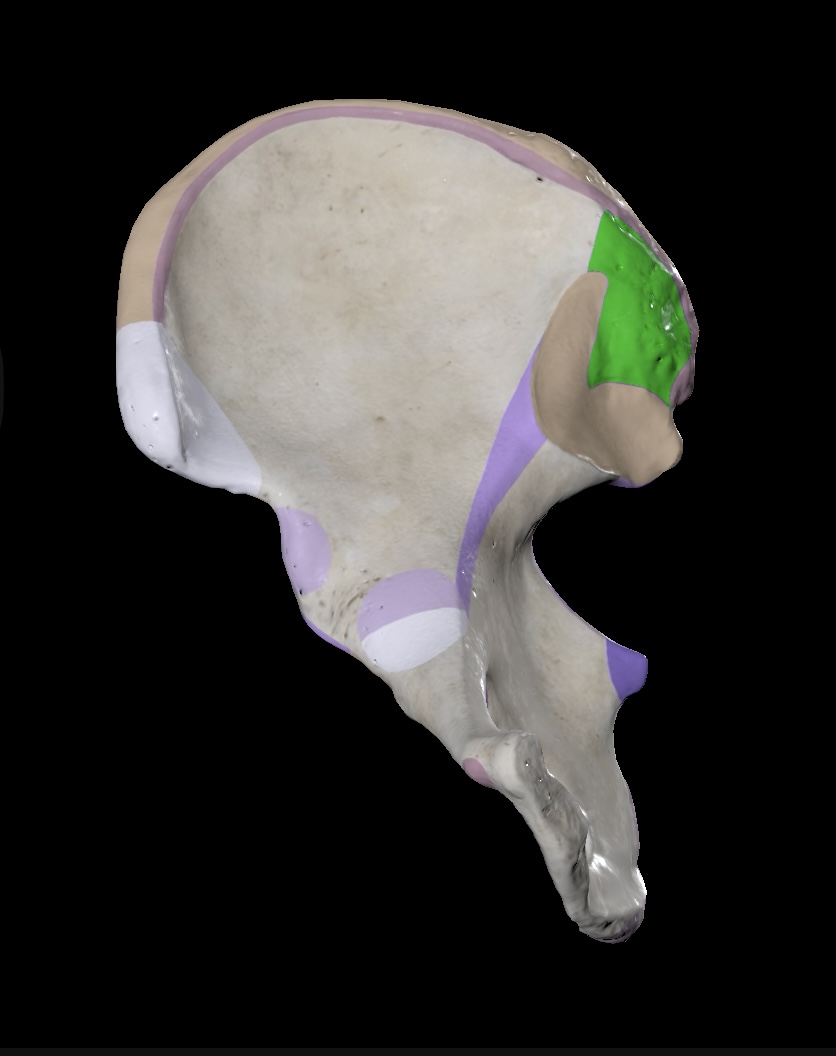

Illium

Ischium

Pubis

Ischial Spine of Ischium

Iliac Tuberosity of Illium

Anterior Superior Iliac Spine

Anterior Inferior Iliac Spine

Posterior Superior Iliac Spine

Posterior Inferior Iliac Spine

Iliac Crest

Acetabulum